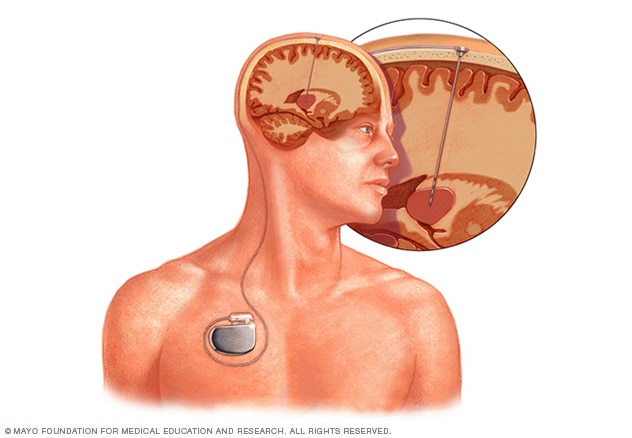

Deep brain stimulation

Deep brain stimulation involves putting electrodes deep within the brain. The impulses from the electrodes help the body manage the brain activity that causes seizures. The electrodes attach to a pacemakerlike device placed under the skin of the chest. The device manages how much stimulation happens.

MRI of deep brain stimulation

A magnetic resonance imaging (MRI) scan of deep brain stimulation shows the location of electrodes placed in the brain.

- Deep brain stimulation. In deep brain stimulation, surgeons implant electrodes into a specific part of the brain, typically the thalamus. The electrodes are connected to a generator implanted in the chest. The generator regularly sends electrical pulses to the brain at timed intervals and may reduce seizures. Deep brain stimulation is often used for people whose seizures don't get better with medicine.